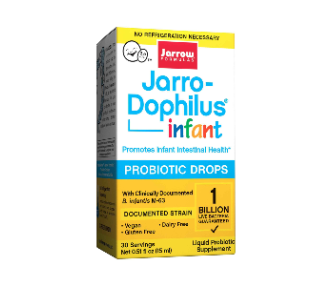

Probiotics, particularly Lactobacillus Bifidus, are first introduced into the sterile intestines of the infant as a result of breastfeeding. Large numbers can soon be observed in the feces of the baby.

Infant thrush

Think always of treating the mother (especially if breastfeeding) with oral supplements of L. bifidus. “Paint” the nipples before each infant feeding with a concentrated culture of L. bifidus.